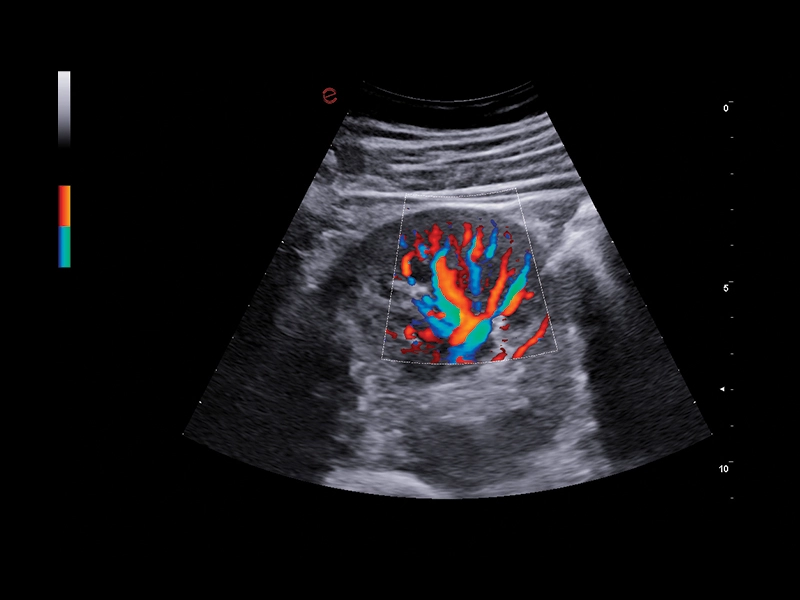

S MyLab™ A50 získáváte možnost provádět široké spektrum vyšetření, včetně jater, srdce, gynekologie a porodnictví, cév, prsu, štítné žlázy, muskuloskeletálního systému, urologie a pediatrie.